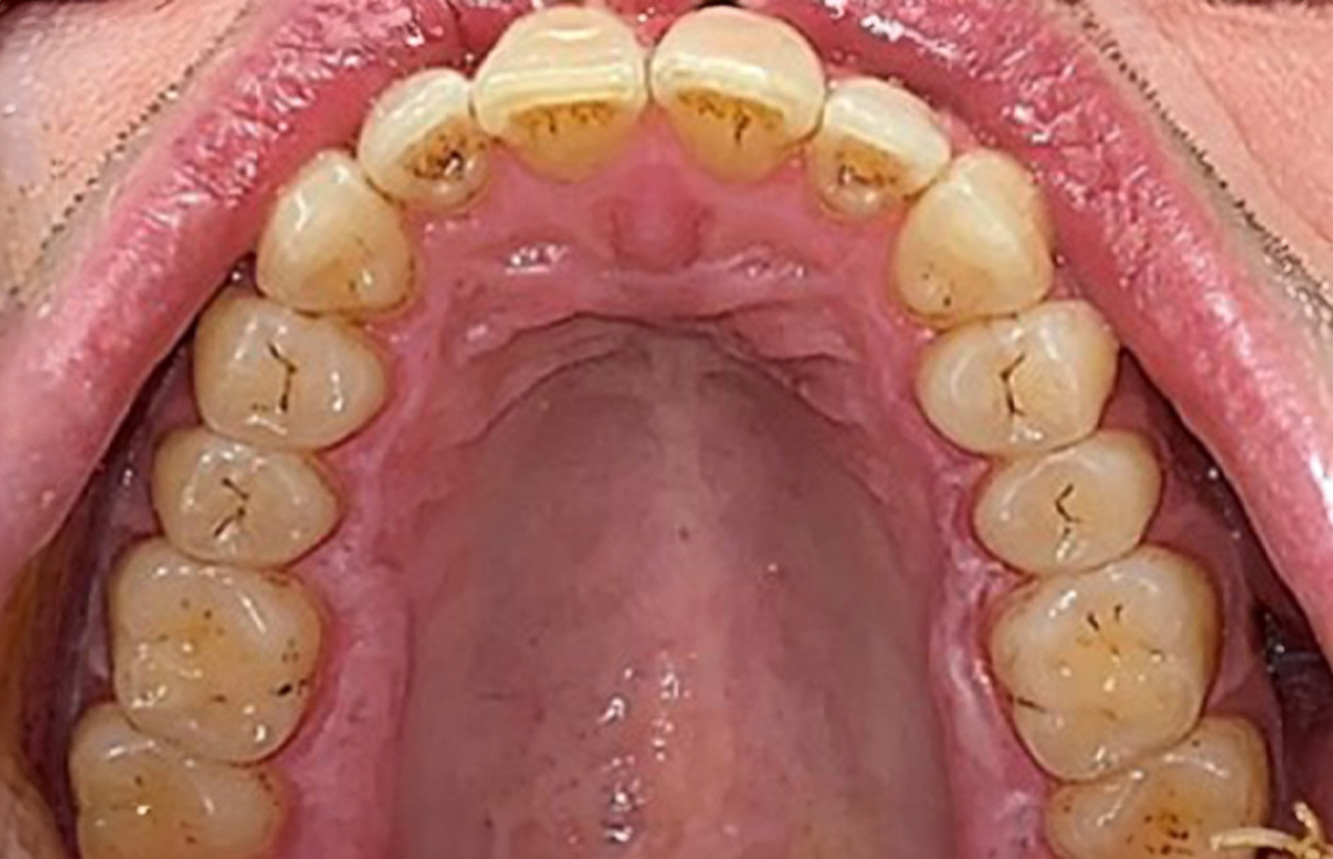

A 71-year old patient presents with having previously undergone a kidney transplant and with a history of hypertonia (high blood pressure). Due to his medical history, long-term medication with cyclosporine is required to suppress the immune system, as well as amlodipine to lower blood pressure. The patient also reports sensitive and bleeding gums. From an oral health perspective, the patient has undergone dental restoration and has eight missing teeth, pronounced gingival growth, and grade B, stage II periodontitis with active pockets and initial root caries on tooth 22. The caries risk assessment determines a moderate risk of caries (API 60). The following treatment recommendations can be determined for the prophylaxis session. more